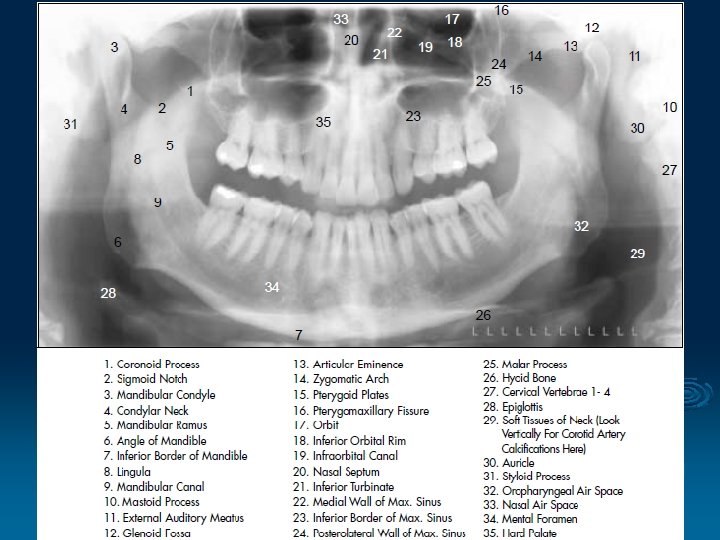

1. Orthopantomography (OPG) § Panoramic extraoral technique § Used to examine both jaws, TMJ, maxillary sinuses and the teeth on a single image § Convenient and inexpensive method with low radiation exposure

Extraoral film = indirect exposure type film § The energy of the x-ray beam is converted into light by intensifying screens (the film is sandwisched between two screens) and this light is used to expose photographic type film § Orthoradial projection – minimizes crown overlapping

§ Patient is positioned with the Franfort plane horizontal, bite peg between the anterior teeth and the chin positioned on the chin support § The film and the tubehead rotate around the patient and produce a series of individual images in a single film